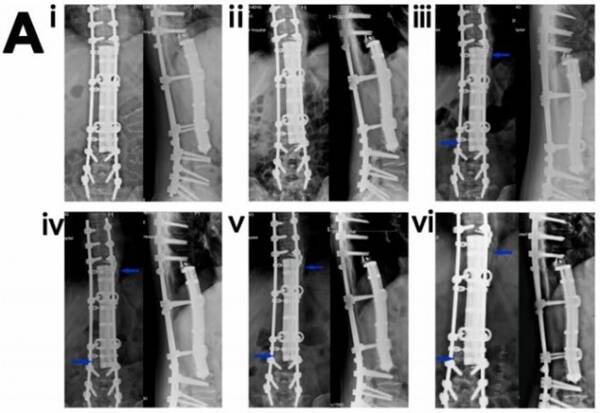

圖1.3D打印多孔Ti6A14V內(nèi)植物重建4 cm股骨缺損的放射學(xué)和生物力學(xué)分析。(A)植入后1個月、3個月和6個月的X線圖像(i-iii)植入后1、3和6個月的計算機斷層掃描圖像(iv-vi)。藍色箭頭表示缺損部位或植入物外表面新形成的骨。(vii)各組的放射學(xué)評分。(n=4)(B)處死后1、3和6個月組的microCT三維重建圖像(i-iii)(灰色表示鈦合金,綠色表示新生骨)。(ⅳ) 各組(n=4)內(nèi)植物周圍和孔內(nèi)區(qū)域骨體積分?jǐn)?shù)的定量結(jié)果。

圖4.3D打印多孔Ti6Al4V內(nèi)植物重建脊柱骨缺損(病例1)。(A) (i-vi)術(shù)后1個月(i)、3個月(ii)、7(個月iii)、12個月(iv)、24個月(v)和32(vi)個月的“內(nèi)植物-骨”X線圖像。藍色箭頭表示內(nèi)植物與骨界面或內(nèi)植物外表面新生骨。(B)術(shù)后3個月(i)、7個月(ii)、12個月(iii)、28個月(ⅳ)、32個月(v)和36個月(vi)的CT圖像。藍色箭頭表示種植體-骨界面或種植體外表面新形成的骨。